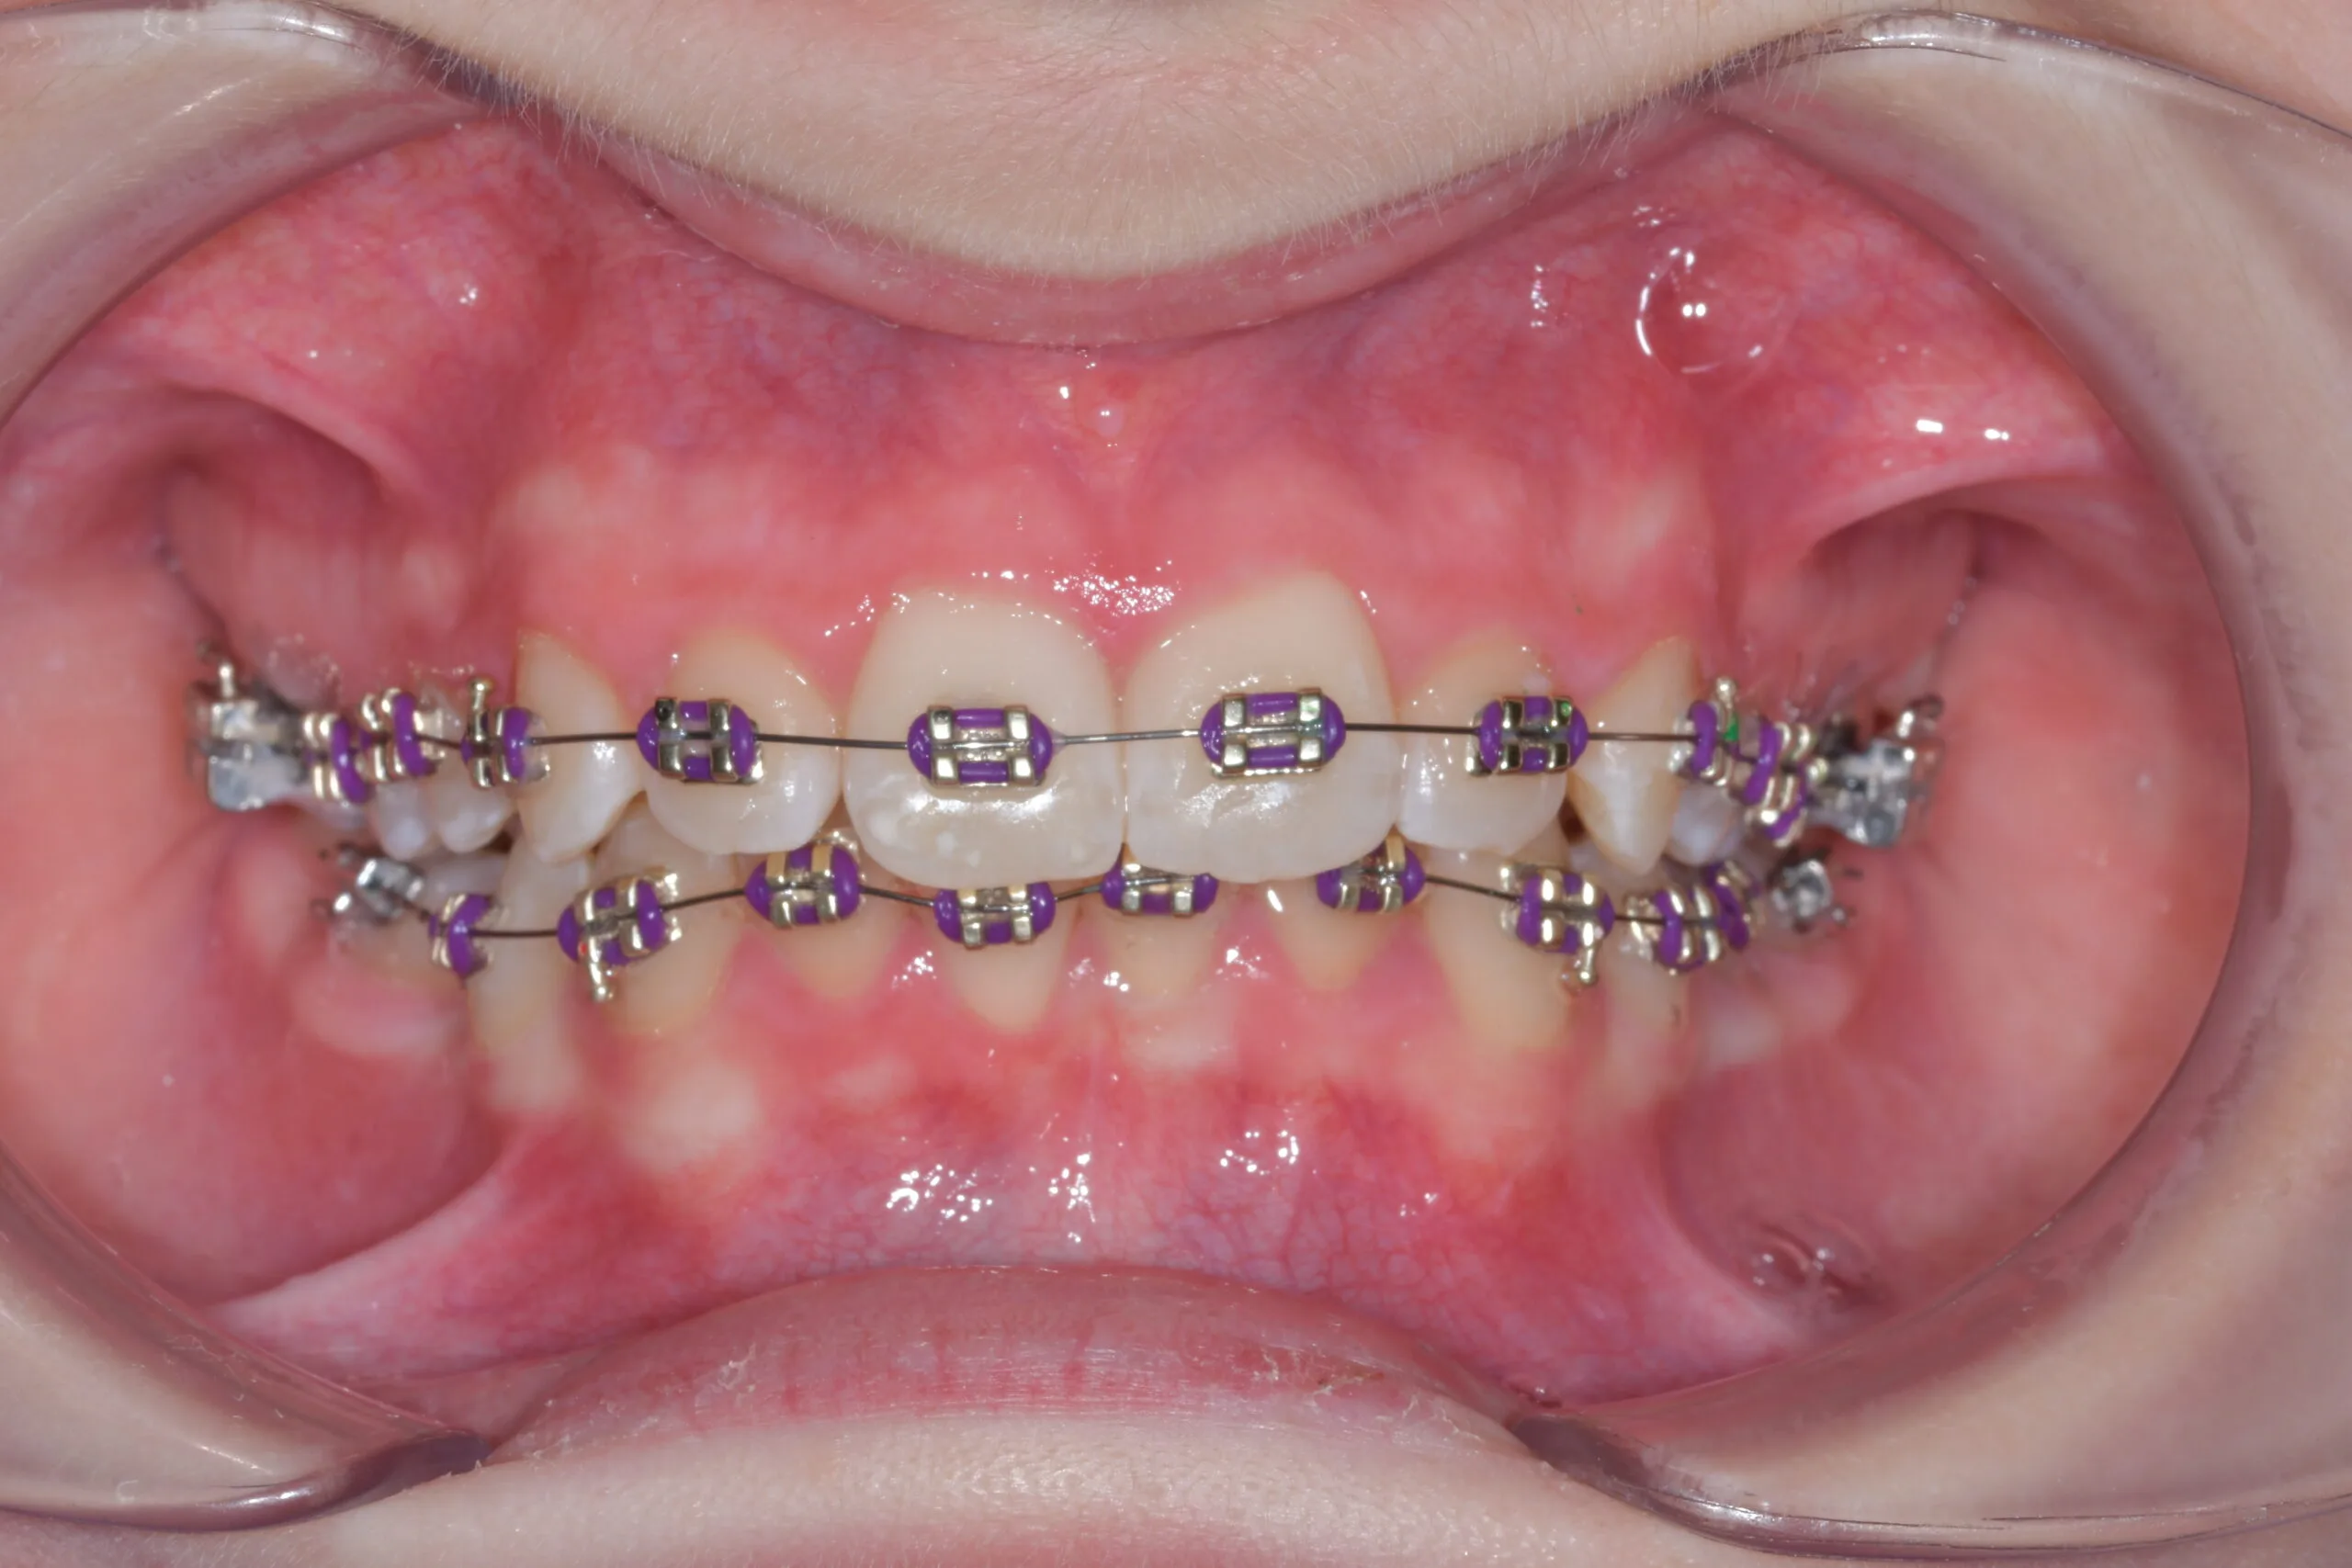

Feste Zahnspangen (Metall, Keramik)

Feste Zahnspangen bestehen aus Brackets, die mit einem Drahtbogen verbunden sind. Sie üben kontinuierlichen Druck auf die Zähne aus und führen sie in die gewünschte Position. Metallbrackets sind robust und oft kostengünstiger, während Keramikbrackets zahnfarben und unauffälliger sind. Eine feste Spange eignet sich für nahezu alle Fehlstellungen und ist besonders effektiv bei Engständen und komplexen Drehungen. Die Dauer der Behandlung hängt von der Schwere der Fehlstellung ab und variiert zwischen 18 Monaten und drei Jahren.